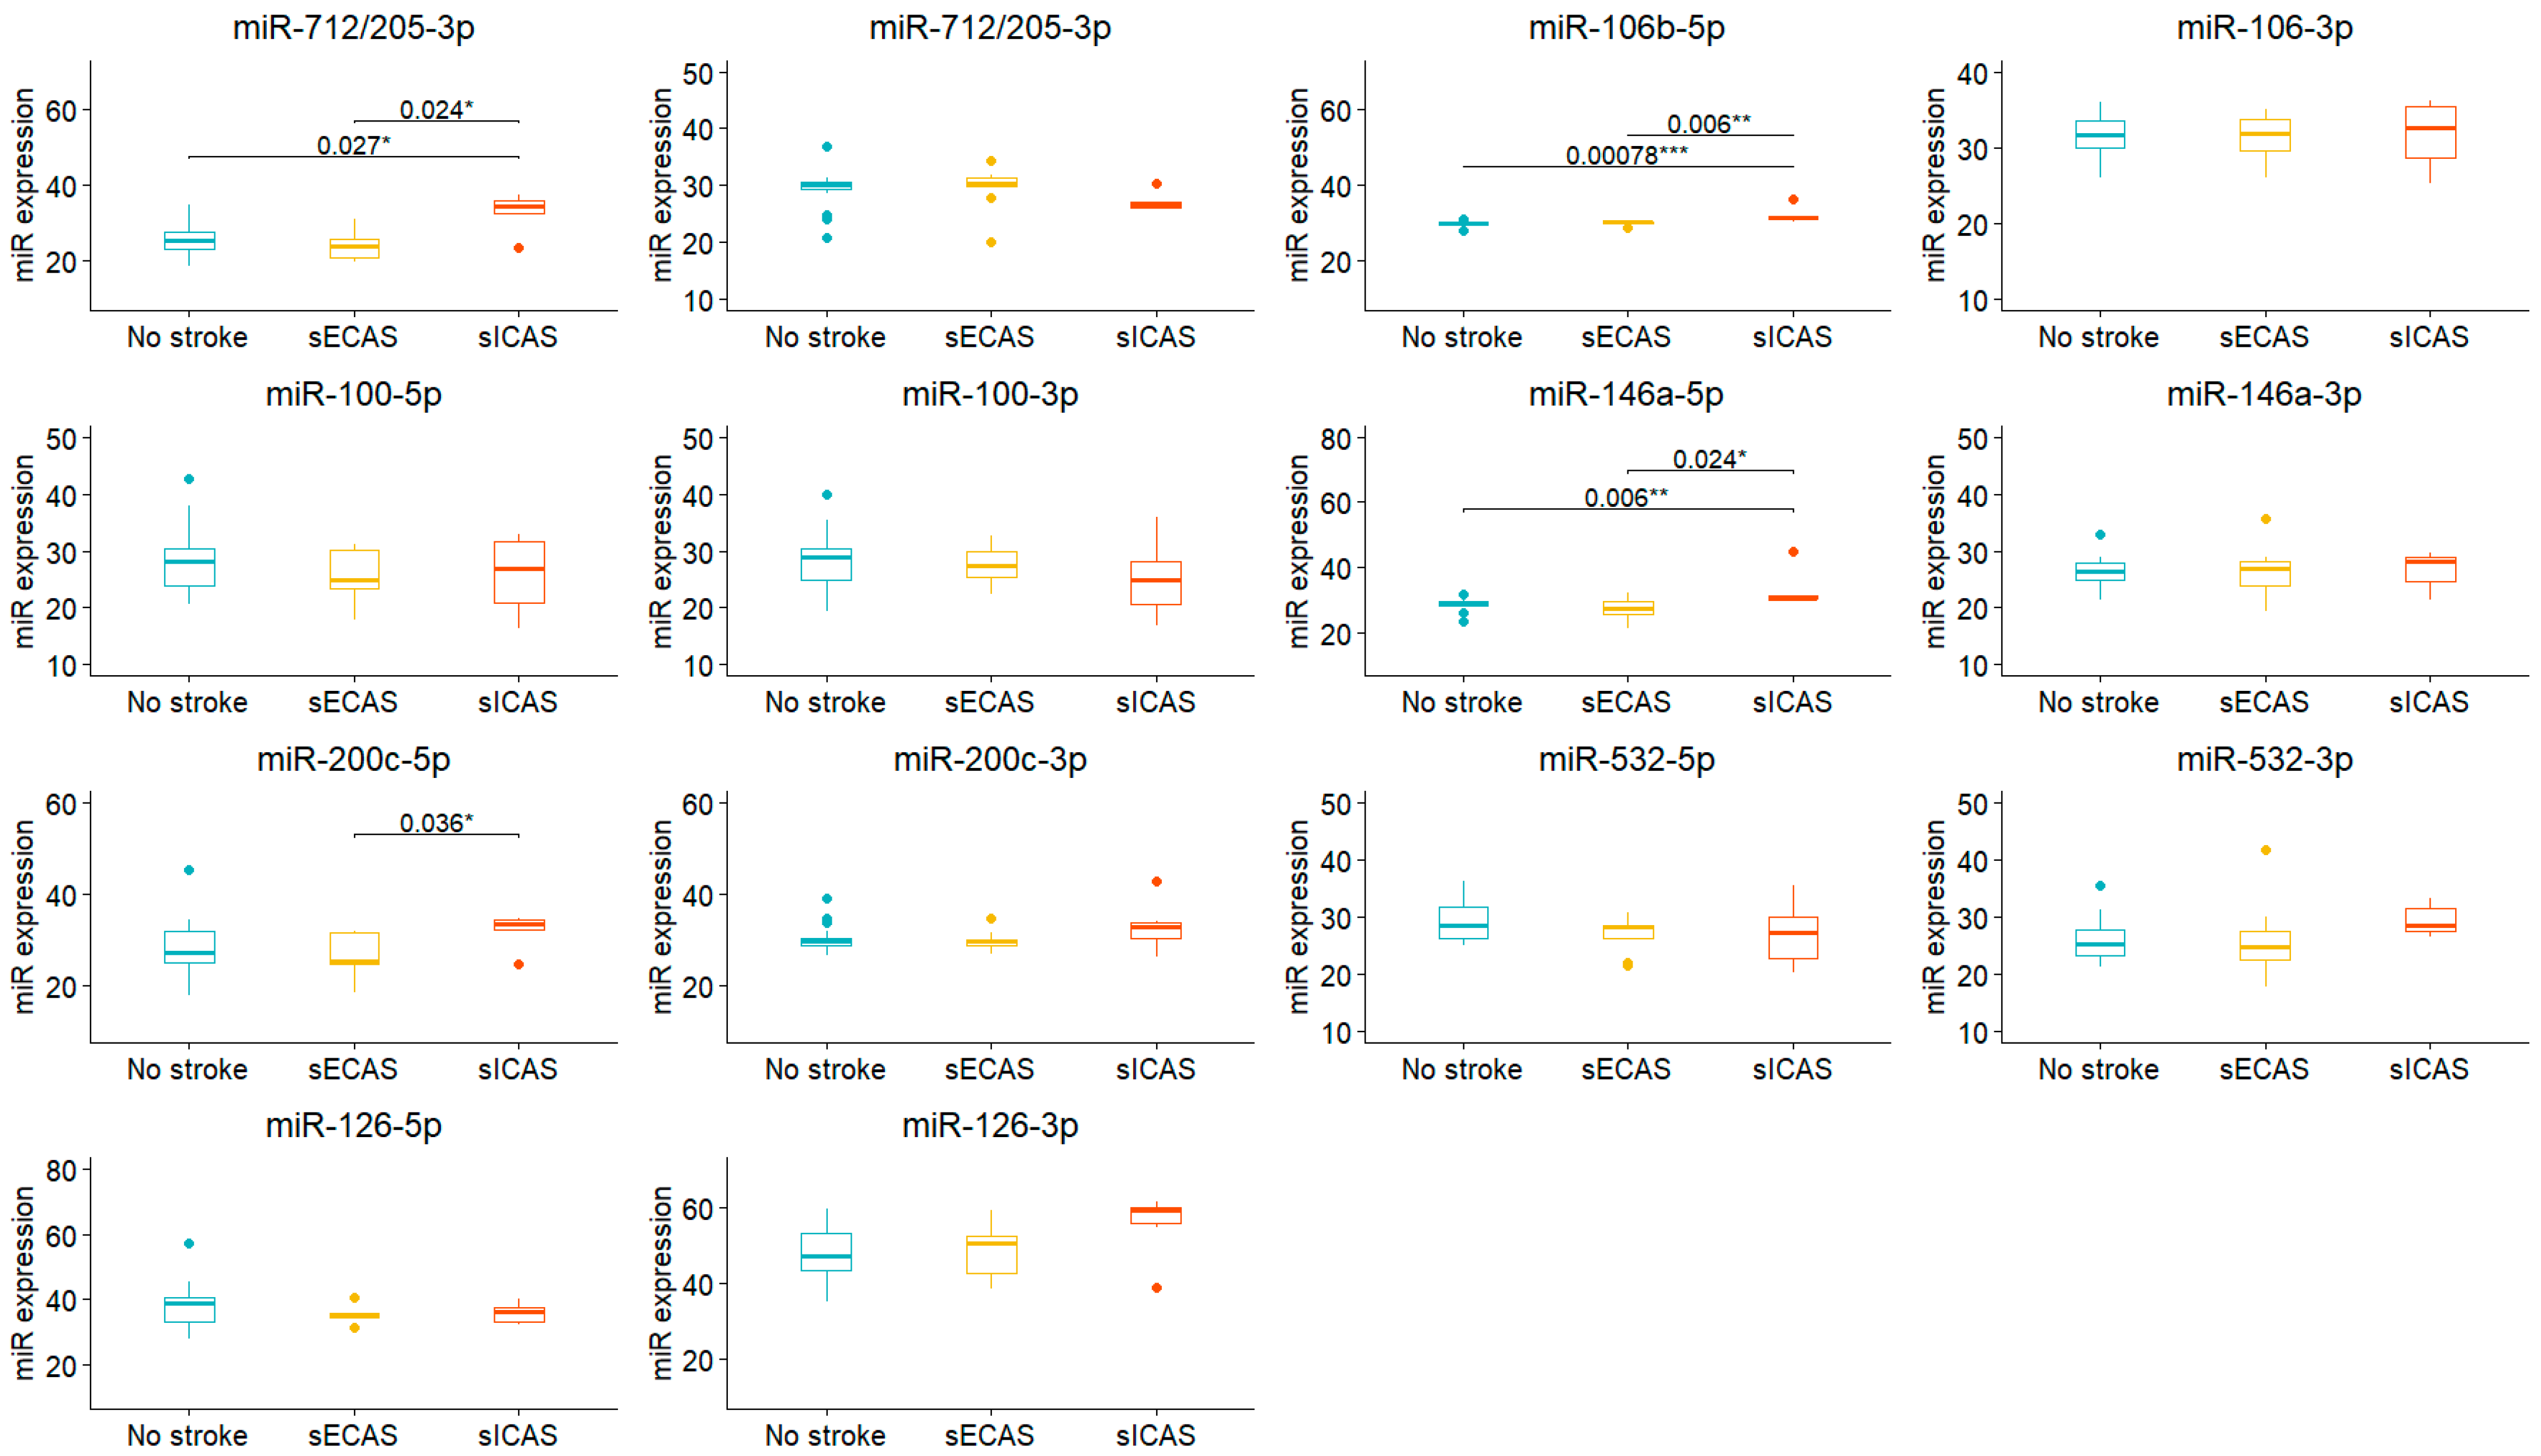

3. Results

| miR-712/205-5p | 23.9 (21.0, 27.9) | 30.0 (24.2, 34.8) | 0.034 |

| miR-712/205-3p | 30.20 (29.47, 30.49) | 27.87 (26.20, 29.81) | 0.037 |

| miR-106b-3p | 31.48 (28.82, 33.38) | 32.26 (27.41, 34.34) | 0.5 |

| miR-106b-5p | 30.03 (29.68, 30.26) | 30.74 (30.24, 31.33) | 0.006 |

| miR-146a-3p | 26.11 (24.19, 28.25) | 27.57 (23.27, 28.68) | 0.8 |

| miR-146a-5p | 28.58 (26.19, 29.47) | 30.06 (29.66, 30.99) | <0.001 |

| miR-100-3p | 28.8 (25.4, 31.0) | 24.7 (22.2, 29.0) | 0.073 |

| miR-100-5p | 26.7 (23.3, 29.9) | 26.7 (23.1, 32.3) | 0.7 |

| miR-200c-3p | 29.64 (28.36, 30.01) | 30.21 (29.25, 33.33) | 0.2 |

| miR-200c-5p | 25.3 (24.6, 31.6) | 32.5 (25.1, 34.4) | 0.019 |

| miR-532-3p | 24.9 (22.8, 27.6) | 28.4 (24.8, 31.8) | 0.071 |

| miR-532-5p | 28.4 (26.2, 30.7) | 27.7 (24.8, 30.2) | 0.5 |

| miR-126-3p | 50 (39, 53) | 55 (45, 59) | 0.073 |

| miR-126-5p | 36.0 (34.6, 40.1) | 36.2 (32.6, 39.7) | 0.7 |